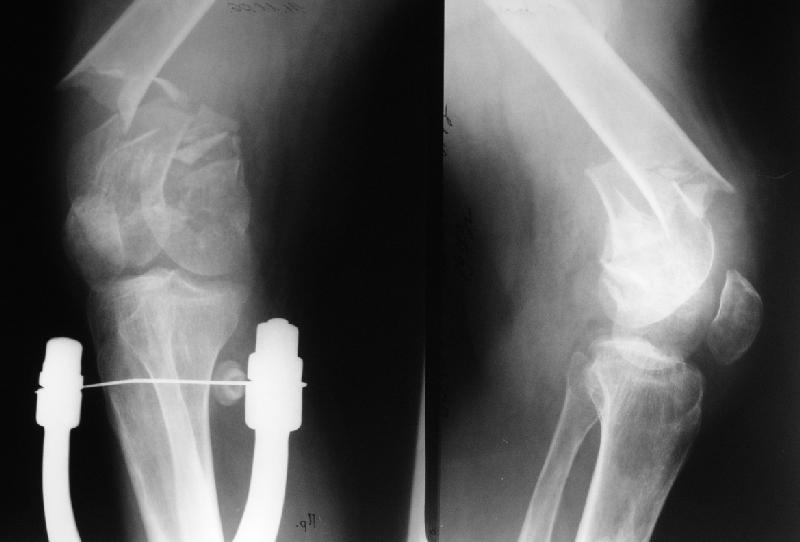

Такие дистальные мы предпочитаем делать антеградно. В дистальном овальном отверстии можно заклинить 2 винта третьим (см. картинку).

> Такие дистальные мы предпочитаем делать антгеградно. В дистальном

> овальном отверстии можно заклинить 2 винта третьим (см. картинку).

В общем согласен, но тогда эндопротезирование оттягивается довольно надолго, т.е. только после удаления антеградного гвоздя.